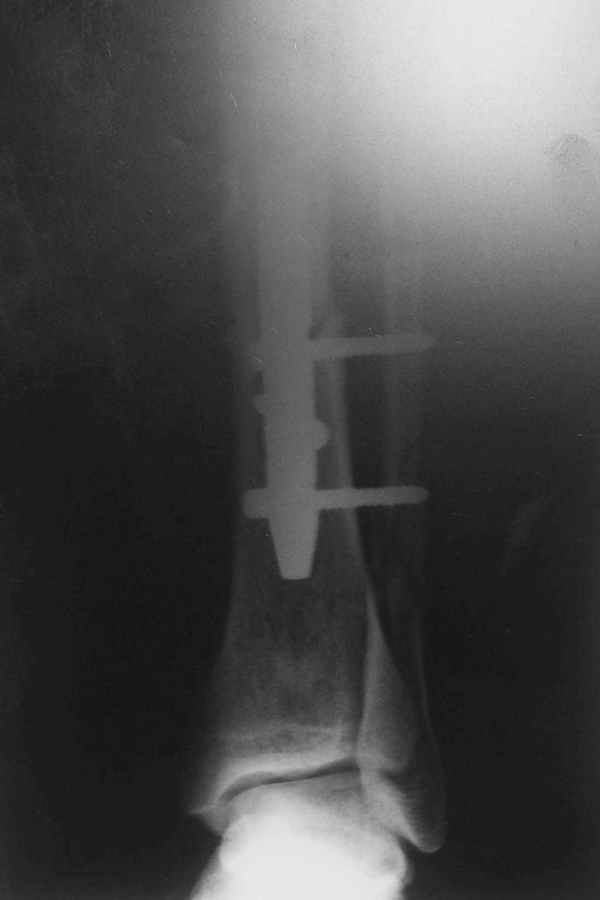

Потекли дистальные винты!

В дистальном отломке три винта( два медио-латеральных и один вентро-дорзальный).

Медио-латеральные вынты - мимо блокирующих отверстий фиксатора, вентро -

дорзальный винт - в отверстии.

Проблемы с верхним дистальным медио - латеральным винтом - он в линии перелома (

перелом косой).

Выполненный остосинтез нестабилен. Штифт надо заменить по "размеру" на солидный, дистльно три запирающих винта. Успехов!

Перелом спиральный, то есть низкоэнергетический, так что со сращением дело обстоит уже неплохо, лишь бы "костоеда" не развилась. Отломки выглядят уже стабилизированными костной мозолью, так что довводить винты, наверно, уже незачем. Разве что при клинической оценке подвижность еще есть - тогда можно для стабилизации наложить простейший аппарат, не опасаясь контакта его элементов с гвоздем, поскольку места в дистальном метафизе оставлено более чем достаточно.